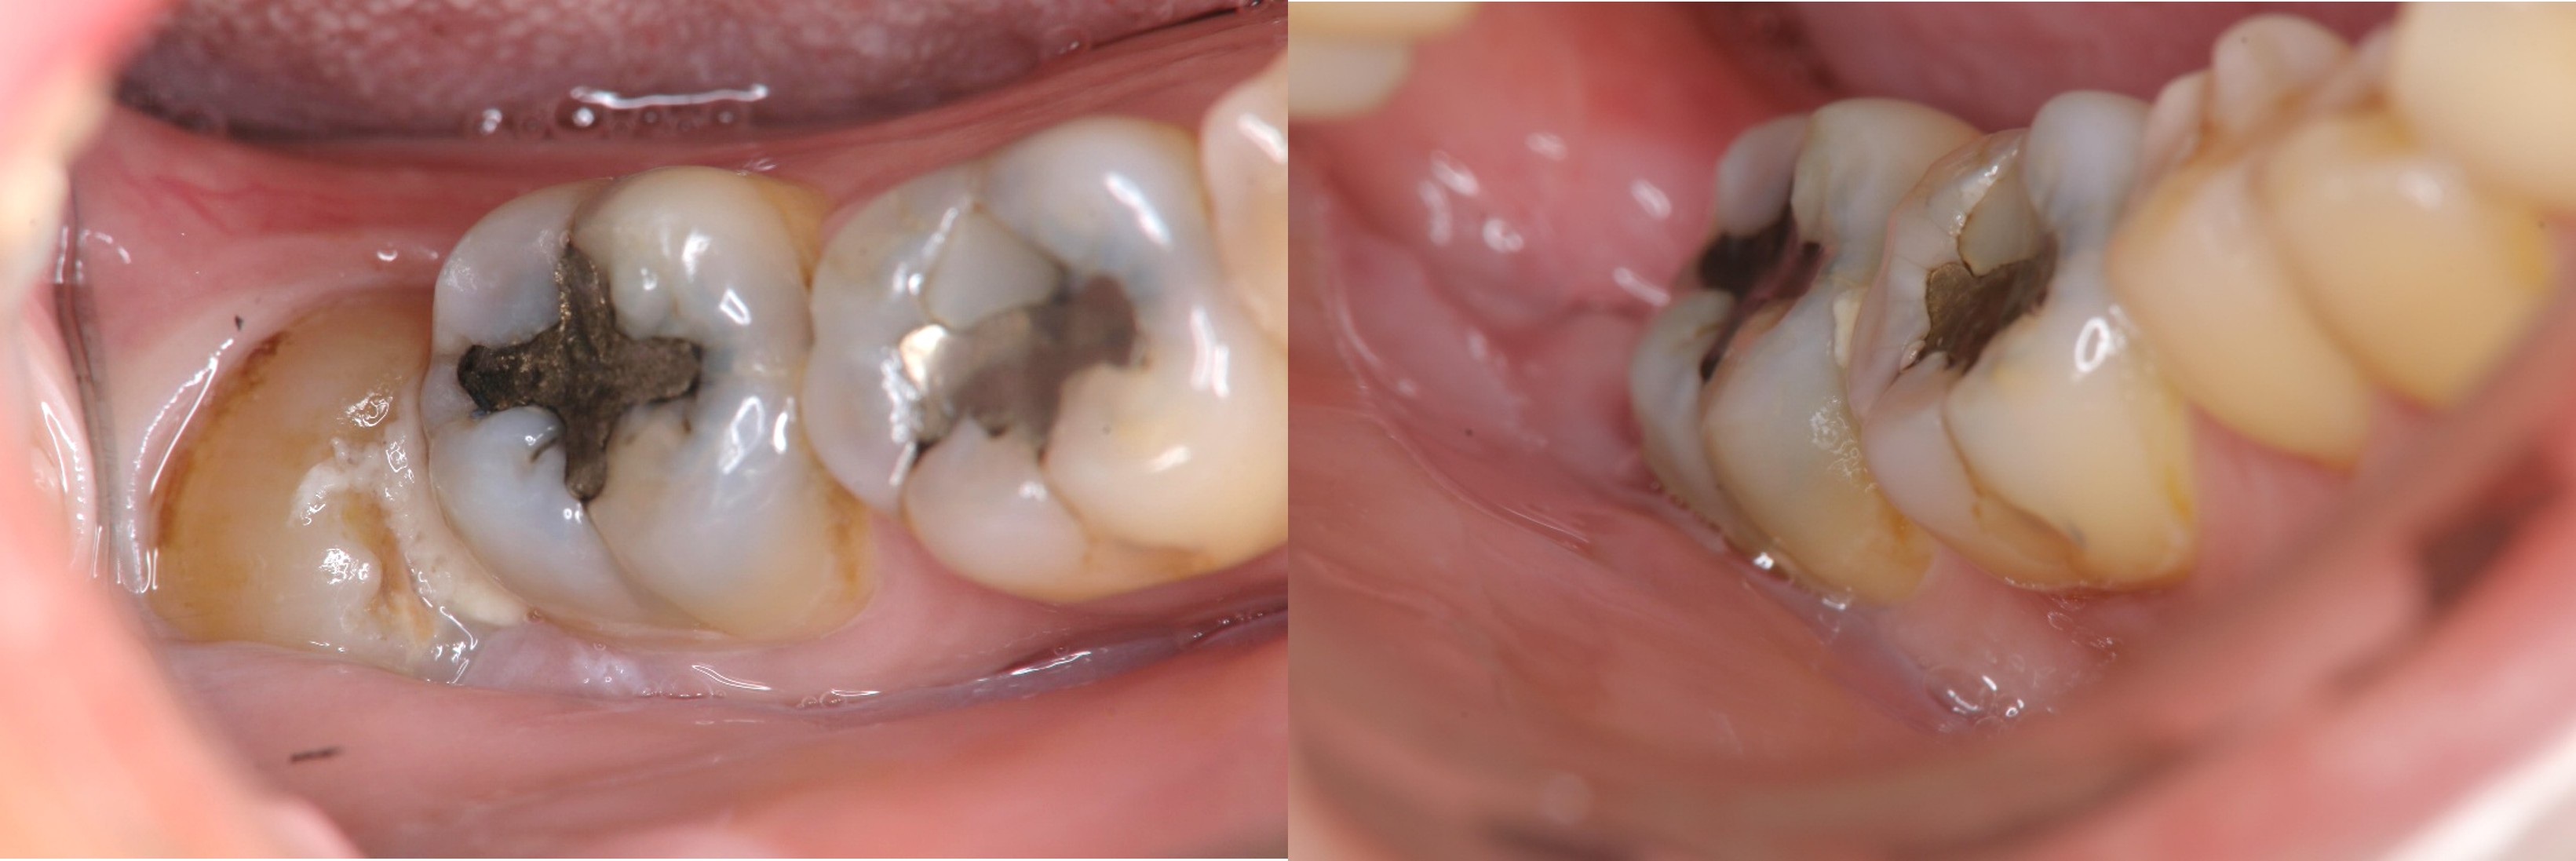

牙髓-膺復合併症-蛀牙-#37

根管治療

牙髓/牙周/膺復合併症